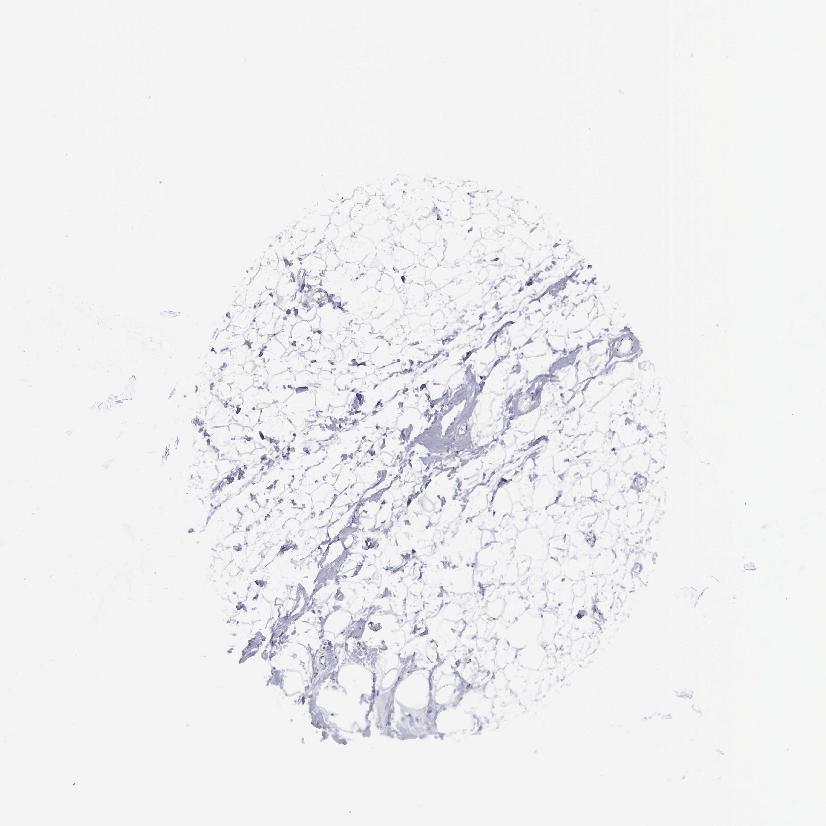

SOFT TISSUE 1 - Antibody stainingi

Antibody staining in the annotated cell types in the current human tissue is reported as not detected, low, medium, or high, based on conventional immunohistochemistry profiling in selected tissues. This score is based on the combination of the staining intensity and fraction of stained cells.

Each image is clickable and will lead to virtual microscopy that enables deeper exploration of all samples and also displays staining intensity scores, fraction scores and subcellular localization as well as patient and tissue information for each sample.

Antibody HPA003524Antibody CAB000458

Fibroblasts MediumNot detected

Peripheral nerve Not detected-